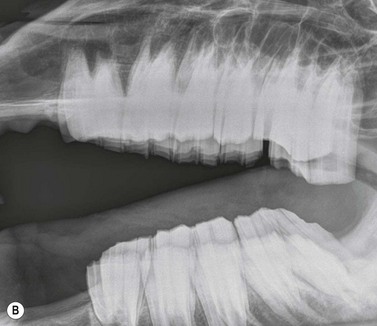

Open-mouthed oblique projections (Figs 13.1413.18)

This radiographic view is used to image the erupted crowns of the cheek teeth and the occlusal aspect of the alveolus (alveolar crest).6 Disorders of the erupted crown such as diastemata, clinical crown fractures, and abnormalities of wear can be imaged.6 The patient must be sedated so that it accepts a Butler’s gag placed between its incisors (Fig. 13.14). Alternatively a short length of hollow PVC tubing or a block of wood can be used to separate the incisors and thus the occlusal aspects of the cheek teeth.

image

Fig. 13.14 Photograph showing sedated patient with a Butler’s gag separating the incisors to allow an open-mouthed oblique dental radiograph to be obtained.

Fig. 13.15 Diagram showing angle of incidence of the X-ray beam to obtain open-mouthed oblique views of the maxillary (blue arrow) and mandibular (red arrow) erupted crowns. The affected side is nearest to the cassette.

Fig. 13.16 Latero10°ventral-laterodorsal open-mouthed oblique view of an aged horse with a supernumerary mandibular cheek tooth (Triadan 12). Note the large overgrowths present on this supernumerary tooth and the excessive wear of the corresponding upper 11.

Fig. 13.17 Open-mouthed oblique view centered on the 05s (wolf teeth) showing large, rostrally displaced and abnormally angulated upper 05s with long thin roots. The Butler’s gag is separating the incisors.

Fig. 13.18 Latero30°ventral-laterodorsal open-mouthed oblique view of a horse immediately after 09 dental extraction. The contents of the mid and more occlusal aspects of the empty alveolus can be visualized without superimposition from cheek teeth of the contralateral row.

The cassette is positioned vertically on the lesion side, close to horse’s head. For these open-mouth views, the X-ray beam is directed in the opposite direction to conventional (closed mouth) oblique views i.e., a dorsolateral–ventrolateral to image the mandibular erupted crowns or a ventrolateral–dorsolateral to image the maxillary erupted crowns. Additionally, the angle of incidence of the X-ray beam is reduced compared to conventional oblique views: latero10°dorsal–lateroventral (ventrally) for mandibular cheek teeth, latero15°ventral–laterodorsal (dorsally) for maxillary cheek teeth. The primary beam should be centered on the rostral aspect of the facial crest and collimated to include all the erupted crowns in the cheek teeth row (Fig. 13.16).

To image the full length of the cheek teeth reserve crowns, open-mouthed oblique projections using approximately the same angles as for standard closed-mouth views may be used, although to prevent superimposition of the contralateral maxillary arcade completely, laterodorsal angles slightly greater than 30° may be required. These projections are also often helpful for examining alveoli for possible dental fragments after dental repulsion (Fig. 13.18). Open-mouthed oblique projections are also useful for imaging the Triadan 05s (wolf teeth) (Fig. 13.17).